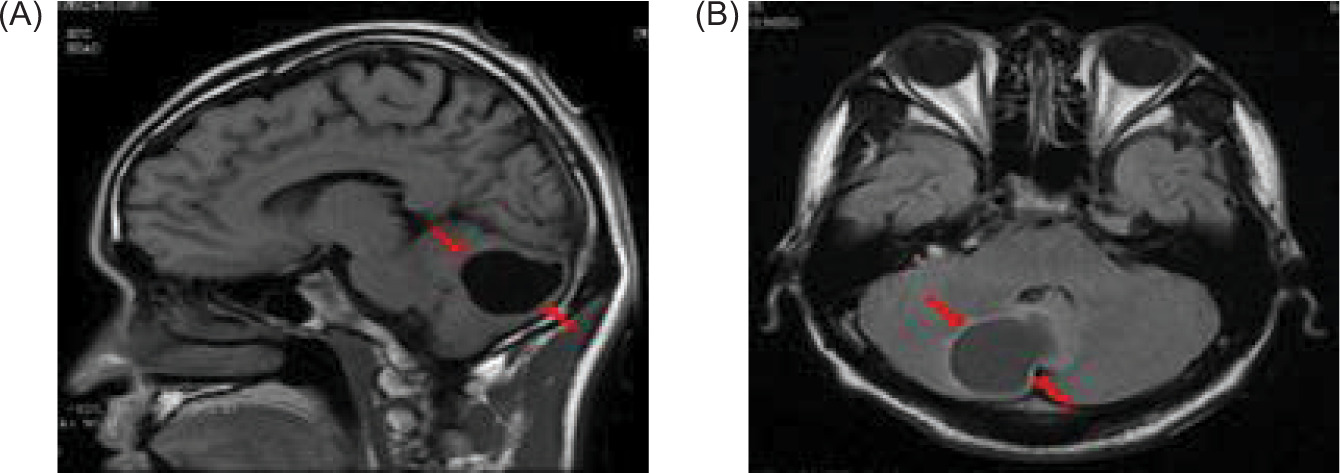

Figure 3: A magnetic resonance imaging (MRI) of the cranial reveals a possible mass in the right temporal bone jugular foramen, with a cross-sectional area of approximately 12×18 mm (red arrow); (A) sagittal position, and (B) flair view.

Figure 6: Magnetic resonance imaging (MRI) of the brain reveals a cystic mass in the right cerebellar hemisphere, approximately 40 mm in size (red arrow); (A) sagittal position, and (B) flair view.